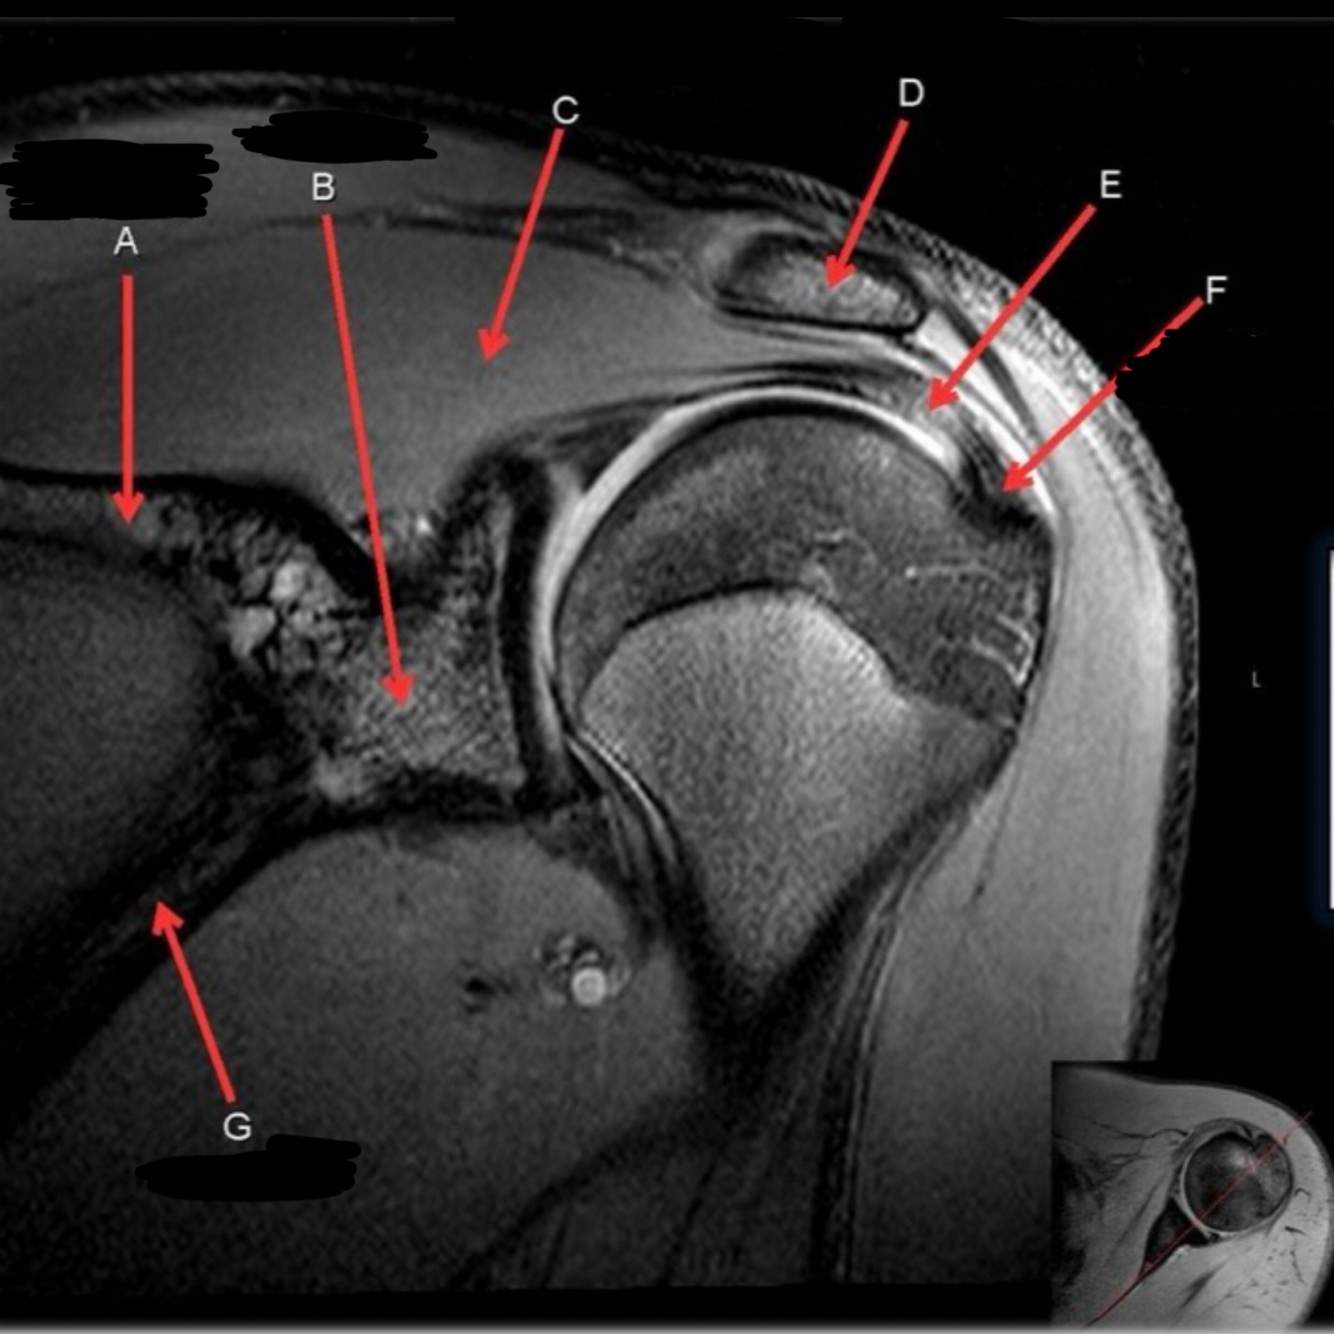

25

What is letter C?

SUPRASPINATUS MUSCLE

26

What is letter D?

ACROMION

27

What is letter E?

SUPRASPINATUS TENDON

28

GREATER TUBEROSITY

29

What is letter G

SCAPULA

30

What is letter A?

CLAVICLE

31

What is letter B?

AC JOINT

32

33

BICEPS TENDON